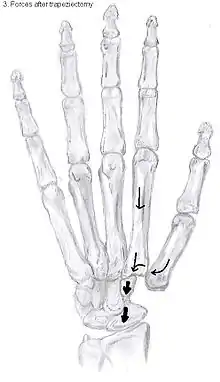

Types of trapeziectomy

The principle of this procedure is the removal of the trapezium bone. It was originally described by Gervis in 1949 [24]. Because half of the carpometacarpal joint is removed, the complaints of patients caused by OA are usually gone.

Trapeziectomy

The most simple form out of the four variations is the trapeziectomy alone, also referred as the simple trapeziectomy.[32] During this procedure, the trapezium bone is removed without any further surgical adjustments.The trapezium bone will be removed through an approximately three centimeter long incision along the lateral side of the thumb. To preserve surrounding structures, the trapezium bone will be removed through fragmentation of the bone (the bone will therefore be broken into pieces).

An empty gap is left by the trapeziectomy and the wound is closed with sutures. Despite this gap, no significant changes in function of the thumb are reported.[31] After the surgery, the thumb will be immobilized with a cast.